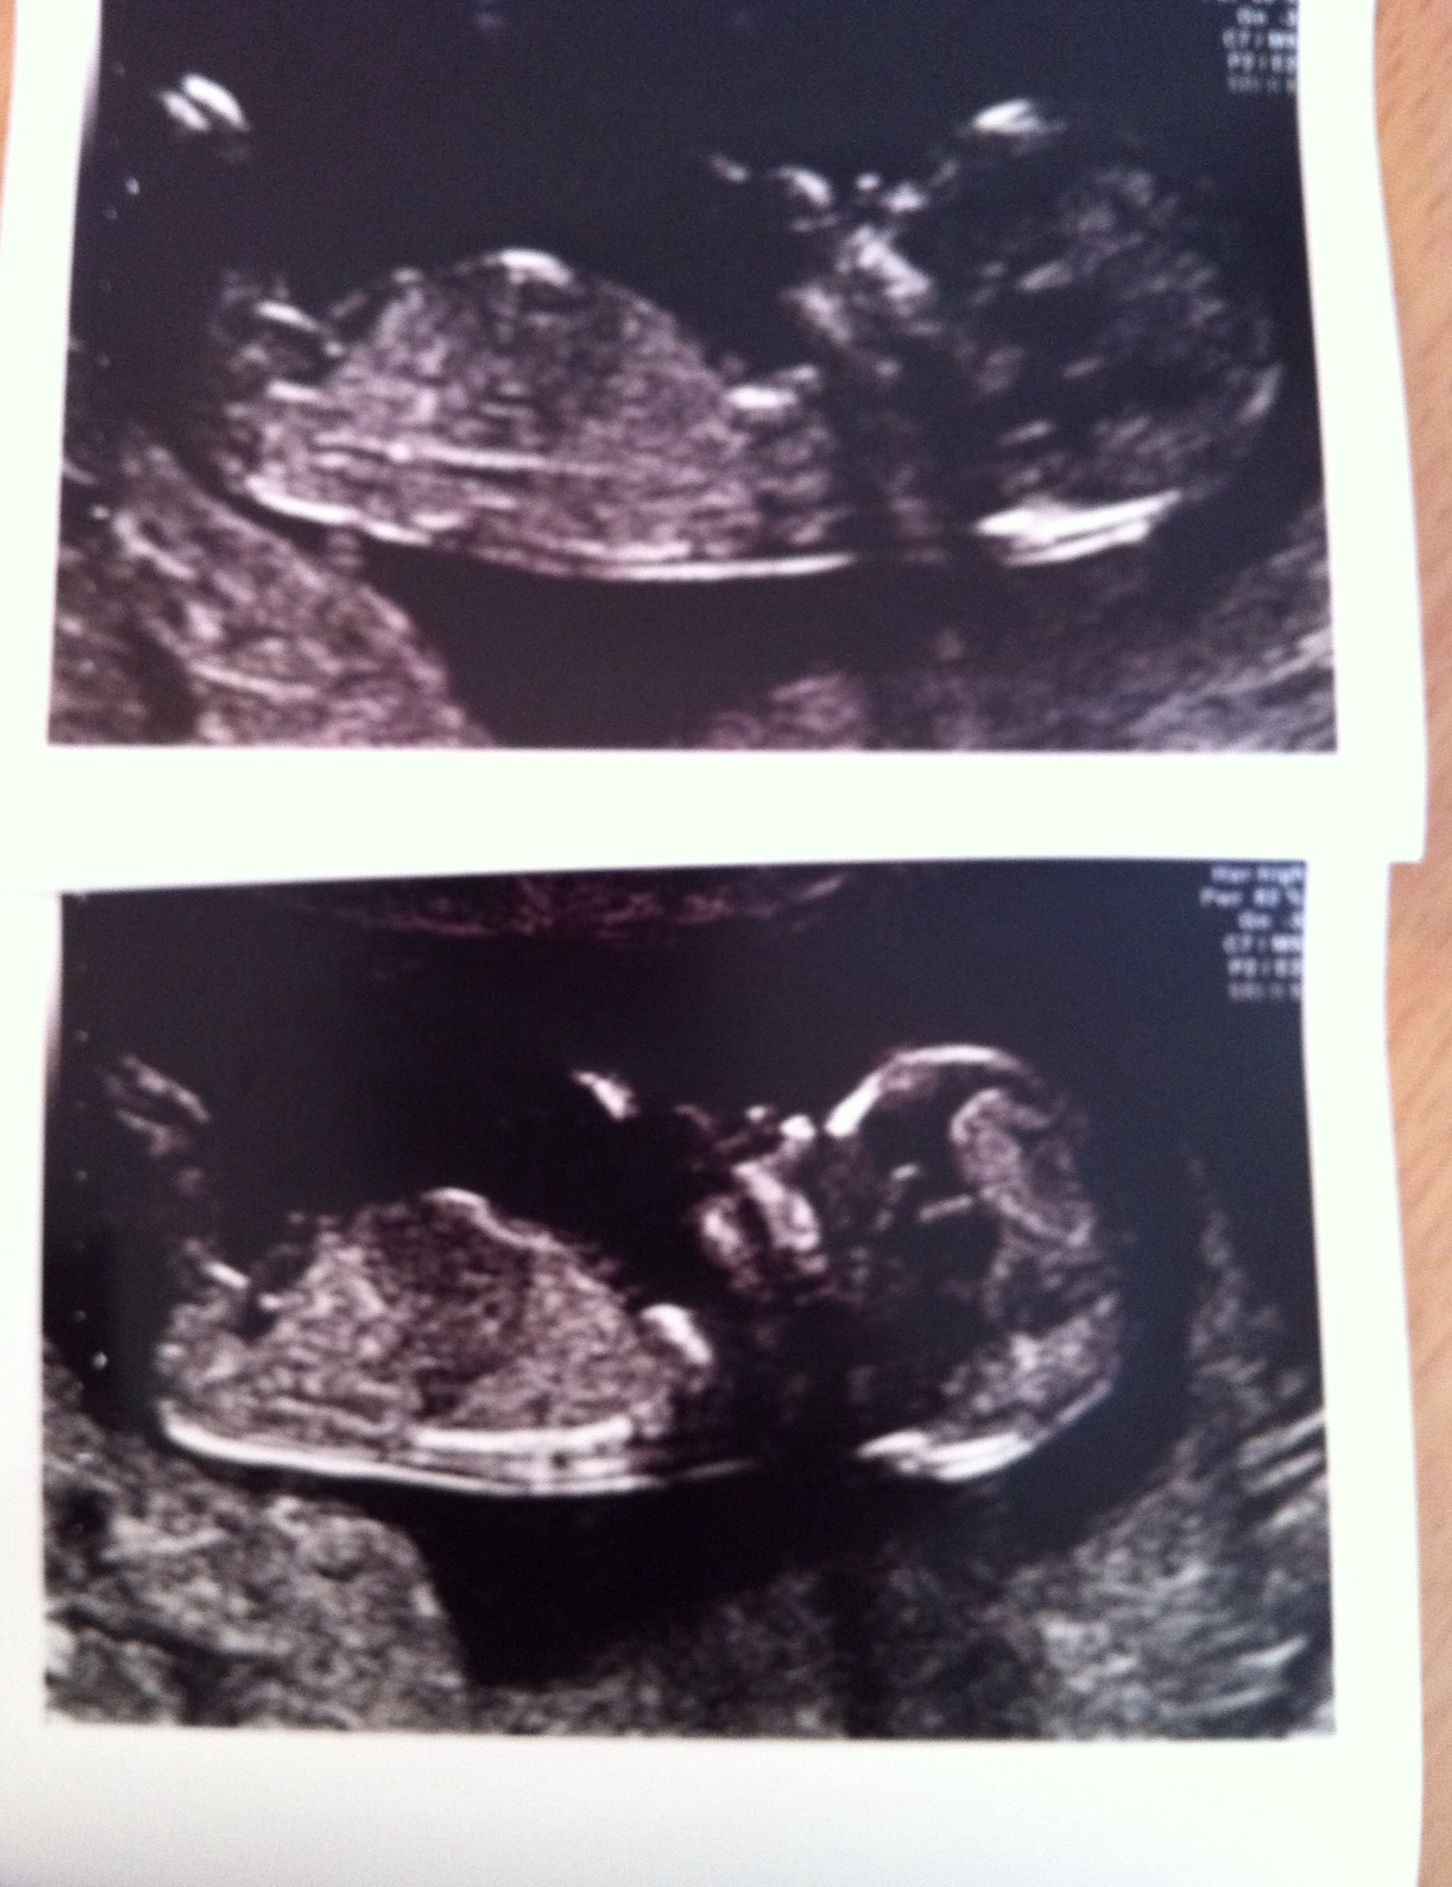

This is baby number 3 , I already have 2 boys , thinking maybe a boy for this one too ?? Xx

If what I'm looking at is the nub, it does look like a lil boy! Did the tech give you any hints?

I'd guess boy as well. More from the second picture than the first.

Looks boyish from the second photo